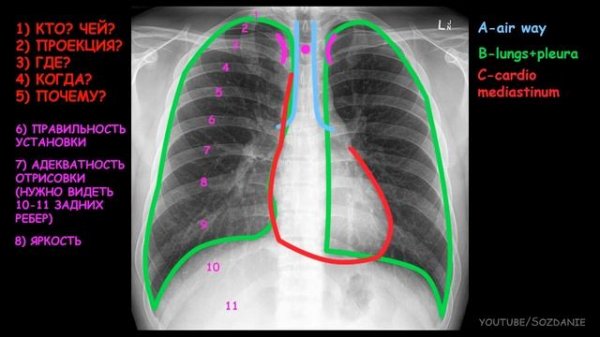

2.1.Рентгеноанатомия грудной клетки.mp4